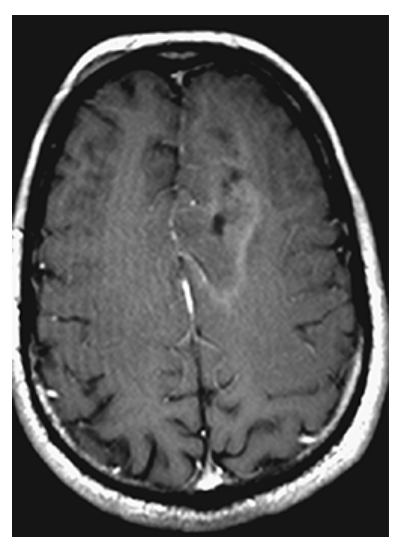

What is A

Arteriovenous Malformation. Axial T1W pre- and postcontrast

What is B

Arteriovenous Malformation. Axial T1W pre- enhanced images show a left frontal lobe mass with surrounding edema, minimal peripheral enhancement, and “worm”-like flow voids.

Arteriovenous Malformation. T2W axial image shows hyperintense edema around the mass of “worm-like” flow voids.